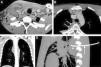

(A) Axial computed tomography (CT) image of the neck showing a collection in the right sternocleidomastoid muscle. (B) Axial CT image of upper chest showing a collection in the anterior mediastinum (asterisk), and another multiseptated collection in the posterior mediastinum (arrows). (C) Coronal reconstruction of chest CT with a better view of the posterior mediastinum collection extending downwards from the head. (D) Sagittal reconstruction of chest CT showing “pigtail” drainage tube (arrow) placed in the posterior mediastinal collection.

A 21-year-old man, consulting due to fever (39°C) and cervical pain, presented a painful mass in the right laterocervical region extending from the mastoid apophysis to the medial end of the clavicle. He had no signs of pharyngotonsillitis or otitis. Of note on laboratory tests were leukocytosis (29000leukocytes/mm3) and neutrophilia (80%). Computed tomography showed a collection affecting the right sternocleidomastoid muscle (Fig. 1A) that extended downwards towards the anterosuperior (Fig. 1B) and posterior mediastinum (Fig. 1C). The sternocleidomastoid muscle and anterosuperior mediastinal abscesses were drained surgically after radiologically guided percutaneous drainage of the posterior mediastinal collection (Fig. 1D). Microbiological analysis confirmed Streptococcus pyogenes infection, and the patient's progress was excellent.